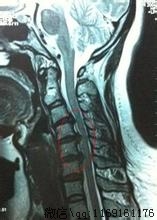

②X线片上显示颈椎生理弧度改变,动力性侧位片上可显示椎间关节不稳、松动(轻度的梯形样改变);

总之,是否是颈型颈椎病,可根据患者发病情况、诱因、病史、体征、X线片及其它辅助检查加以区别,尤其是X线片,在鉴别诊断上具有较高的价值。